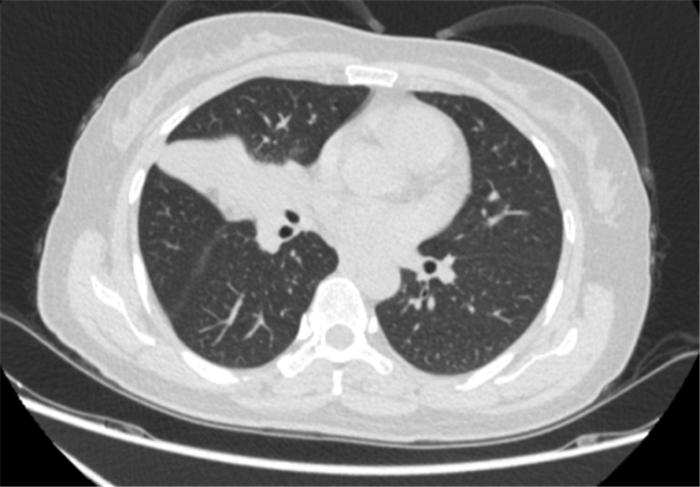

经过4个周期的治疗后复查发现:李女士的病灶明显缩小,实现了降低肺癌分期。

免疫联合化疗新辅助治疗4周期后胸部CT

肿瘤缩小降期,无疑为李女士打开了新的“生命之门”。经过评估后,心胸外科郭建极教授、阳诺博士团队为她行胸腔镜下右肺下叶切除术+纵膈淋巴结清扫术。

令人欣慰的是,术后病理提示送检肺组织为伴多量淋巴细胞浸润的大片坏死组织,未发现肿瘤残存,且淋巴结同样未见癌转移,术后病理分期达到了完全缓解。术后,李女士继续接受辅助免疫单药维持治疗,不仅安全而且耐受性良好。